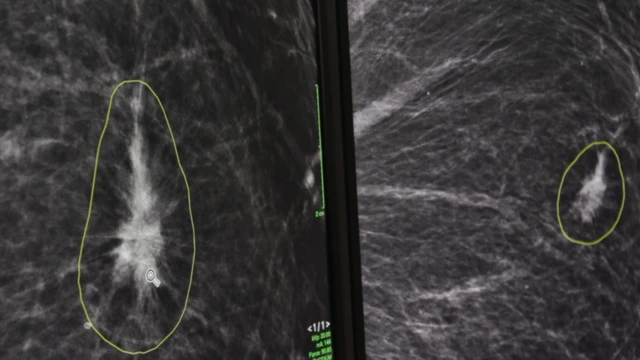

وقد شرح الدكتور ليب لبرنامج بي بي سي كليك كيفية عمل تقنية الذكاء الاصطناعي باستخدام نتائج فحص ماموغرام لسيدة بدون الكشف عن هويتها.

"ما نراه الآن هو عبارة عن صورتي ماموغرام أخذتا من الجانب الأيمن والجانب الأيسر، وما نبحث عنه هو الاختلافات".

ومن خلال الضغط على زر، يستطيع أطباء الأشعة رؤية وفحص الاختلافات التي رصدها الذكاء الاصطناعي بين الصورتين.

وأشار الدكتور ليب إلى منطقة أحاطها برنامج الذكاء الاصطناعي بدائرة، وحددها على أنها المنطقة الرئيسية المثيرة للقلق.

وأضاف: "عند إجراء الفحوص، الهدف هو تحديد المشكلات في مهدها وقبل أن تتفاقم".